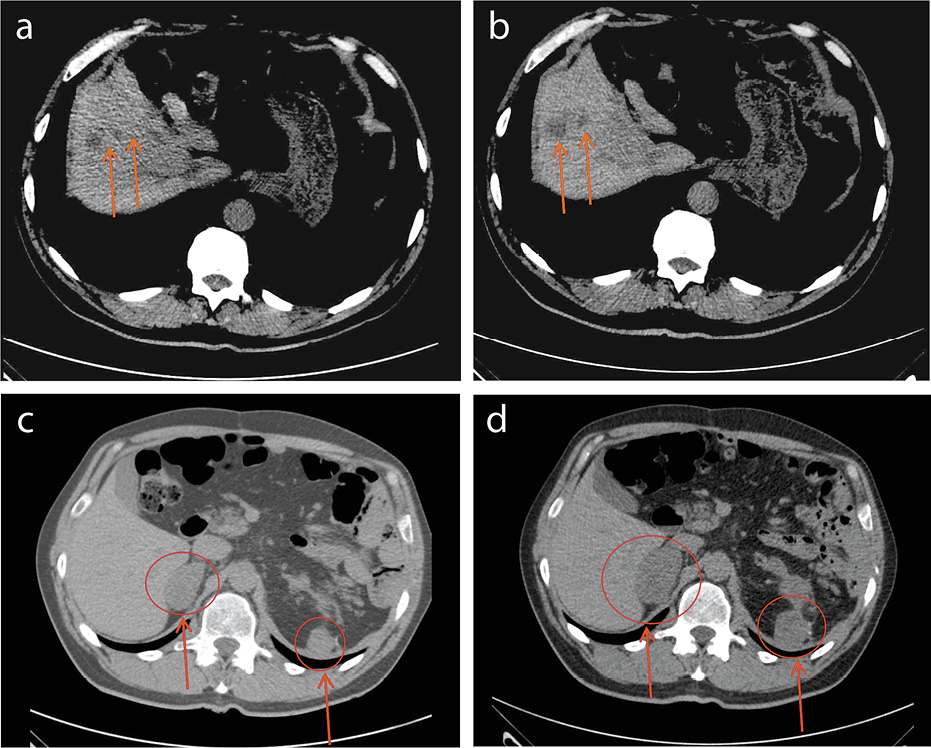

По данным контрольного обследования через 6 мес иммунотерапии отмечен регресс опухоли в рамках частичного ответа (рис. 3), болевой синдром в подглазничной области слева исчез без использования анальгетиков.

Рис. 3: а, b – значимое уменьшение таргетного очага в проекции правого надпочечника и исчезновение опухоли в проекции зоны резекции (а – через 4 мес иммунотерапии; b – через 6 мес иммунотерапии); c, d – уменьшение объема опухоли в левой верхнечелюстной пазухе (c – через 4 мес иммунотерапии; d – через 6 мес иммунотерапии).

Полный ответ опухоли на терапию ниволумабом отмечен через 12 мес после начала лечения. Общая продолжительность иммунотерапии составила 2 года.